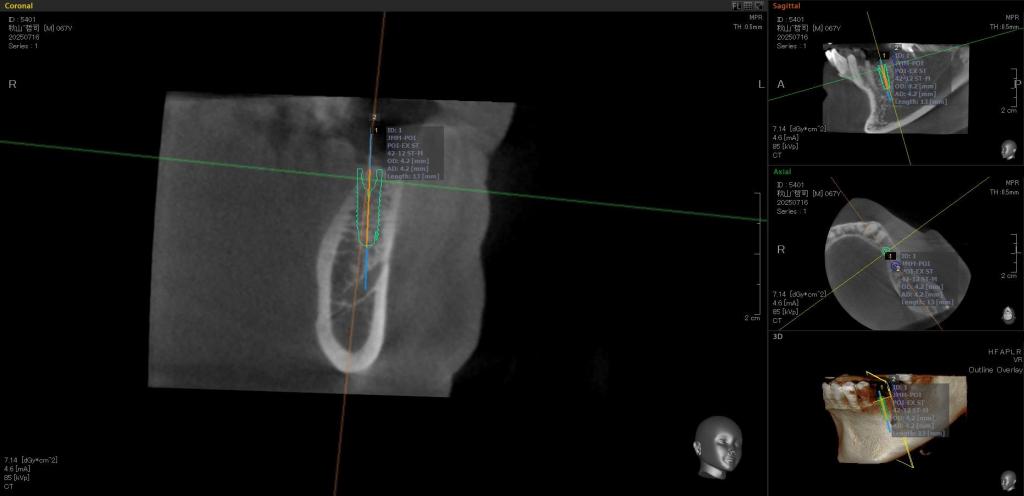

- 抜歯後3ヶ月ほど経過してCTを撮影しました。

抜歯時「抜歯窩保存法」という処置をしていたので、骨の幅、高さ、充分に確保されていました。